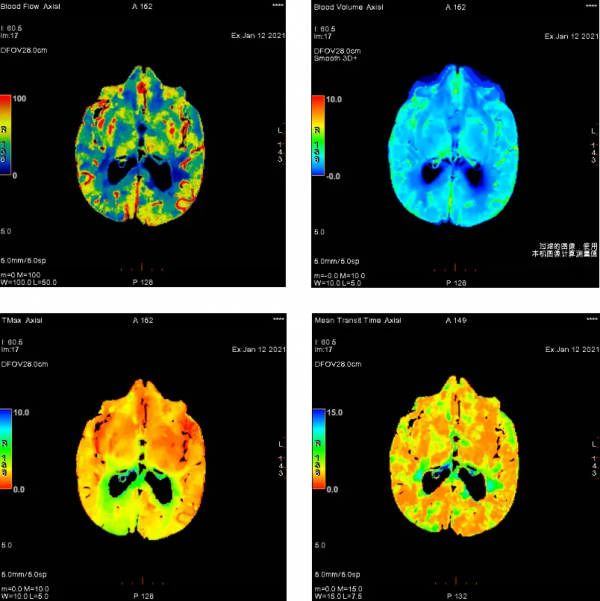

病例1:頭頸部CTA示左側頸總動脈分叉部、右側頸內動脈起始段侷限性輕度狹窄,雙側大腦中、前、後動脈未見明確狹窄;頭顱CTP示雙側腦血流灌注大致對稱。